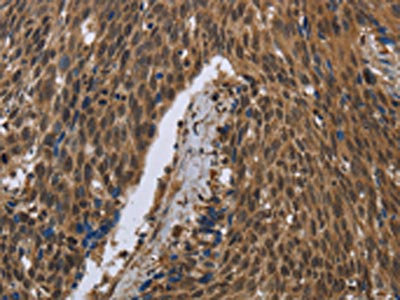

IHC (Immunohiostchemistry)

(Immunochemical staining of human GCDFP 15 in human hepatoma with rabbit polyclonal antibody (1:1000, formalin-fixed paraffin embedded sections).)